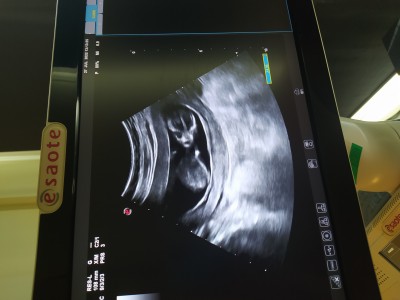

Cinsiyet tahmini böyle anlayanlar vaemi

13 haftada bebek cinsiyet böyle anliyan varmi

Gebelik haftası

13

Kesen uzun kızlarda daha yuvarlak oluyo bence kesin bilgi değil tabi ama erkek gibi geldi bana :)

Kese cinsiyet hakkında bilgi vermiyor canım hurafeler onlar. Ultrason cihazı bastırınca kese bükülebilir su dolu balon gibi şekli oynar sürekli :)

Doğrudur canım ben tahminde bulundum gördüğüm ultrasonlara bakarak içimden geçeni söyledim en doğru tahmini doktor yapar tabiki :)

Ben de kese doğru sanıyordum sonra doktorum güldü o ultrason ucuyla keseyi oynattı anlattı :)))) Allah herkese sağlıkla gönlüne göre versin inşallah :)

Cinsiyet için yeterli bi fotoğraf değil çünkü bacak arası gözükmüyor ve nub çıkıntısı da gözükmüyor